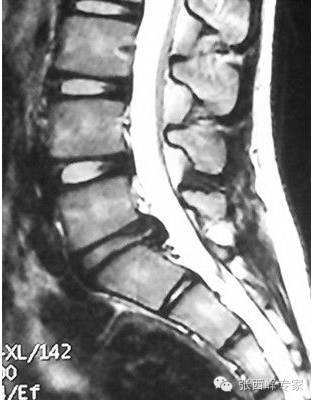

第二例:2004年7月6日出生。

主诉:腰痛半年,加重伴腿痛1月

不可思议,这么小的孩子,影像学确诊是腰椎间盘突出症。